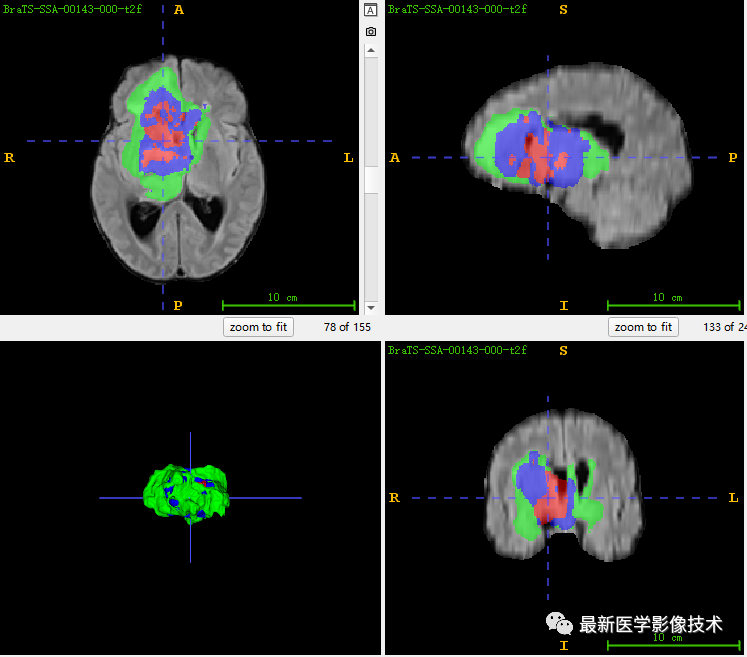

6、验证集分割结果

左图是金标准结果,右图是网络预测结果。

7、测试集分割结果